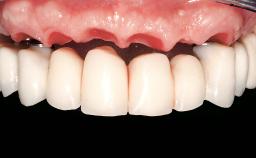

Immediate Loading of Eight Implants in the Maxilla and Six Implants in the Mandible and Final Restoration with Three-Unit and Four-Unit FDPs

Prosthesis Type FDP

Defining Characteristics Fully edentulous upper jaw to be rehabilitated with an implant-borne fixed dental prosthesis

Loading Protocol Immediate